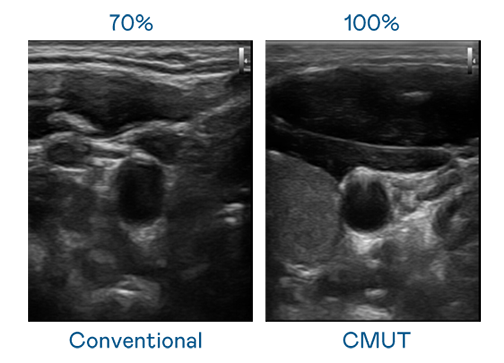

CMUT 技术是一种用电容式微机电元件来产生超音波讯号的技术。与传统 PZT 压电式技术相比,CMUT 频宽增加 30%,更宽频的超音波讯号让影像解析度大幅提升,是实现高影像品质医疗超音波扫描、促进精准医疗发展的关键技术。

超音波影像的解析度高低,首先取决于探头能发出的讯号频宽。省港流鸢粤语高清 CMUT 可提供高清晰的超音波讯号,提供高频宽、高灵敏度、影像纹理细节更高的超音波影像,协助医护人员缩短影像判读时间及利用精准的医疗影像进行诊断。